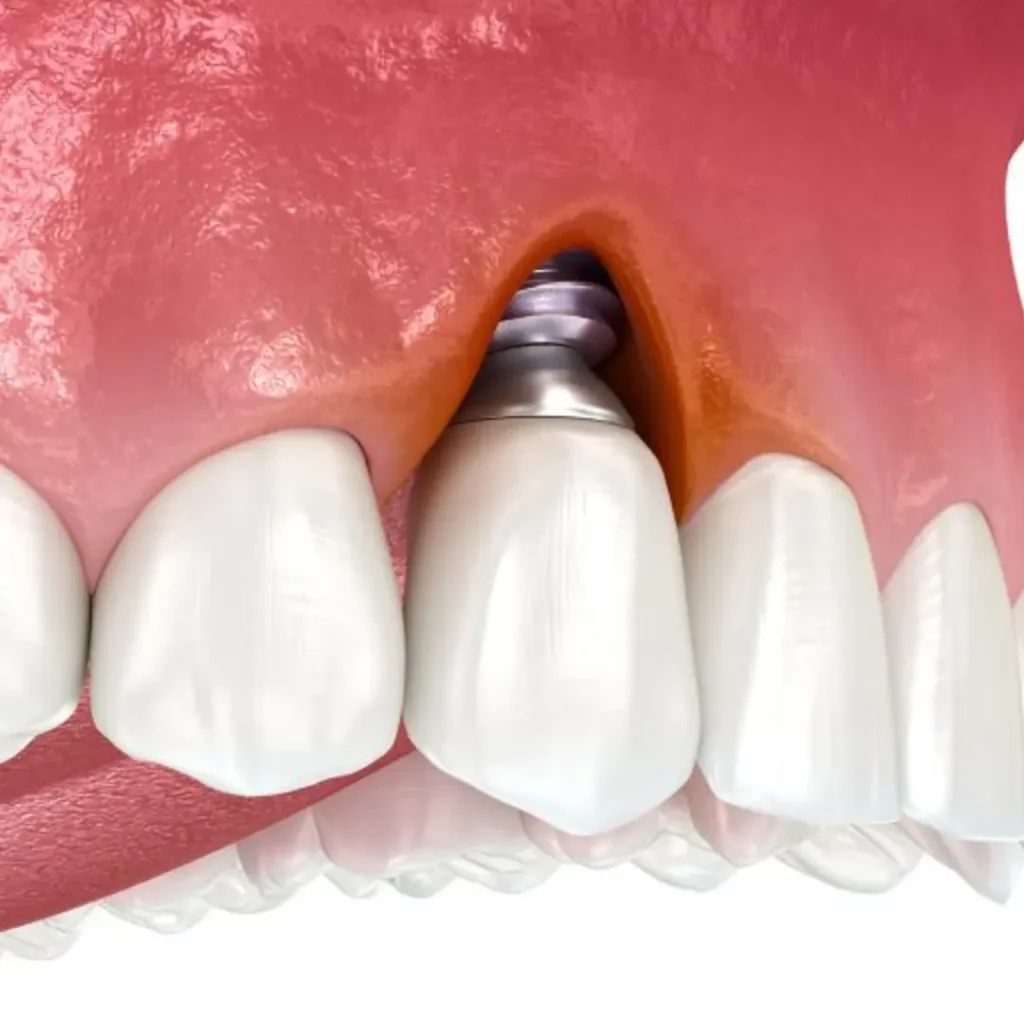

Can gum disease affect my dental implant?

Yes. Gum disease (also called peri-implantitis when around an implant) can compromise the success of your dental implant by damaging the surrounding soft tissue and bone. Early detection and treatment are key to saving the implant.

Is it possible to get an implant immediately after tooth loss?

Yes, in some emergency cases, we can place an implant immediately after extraction, provided the bone and soft tissue conditions are favorable. This is called immediate placement and reduces the number of visits.